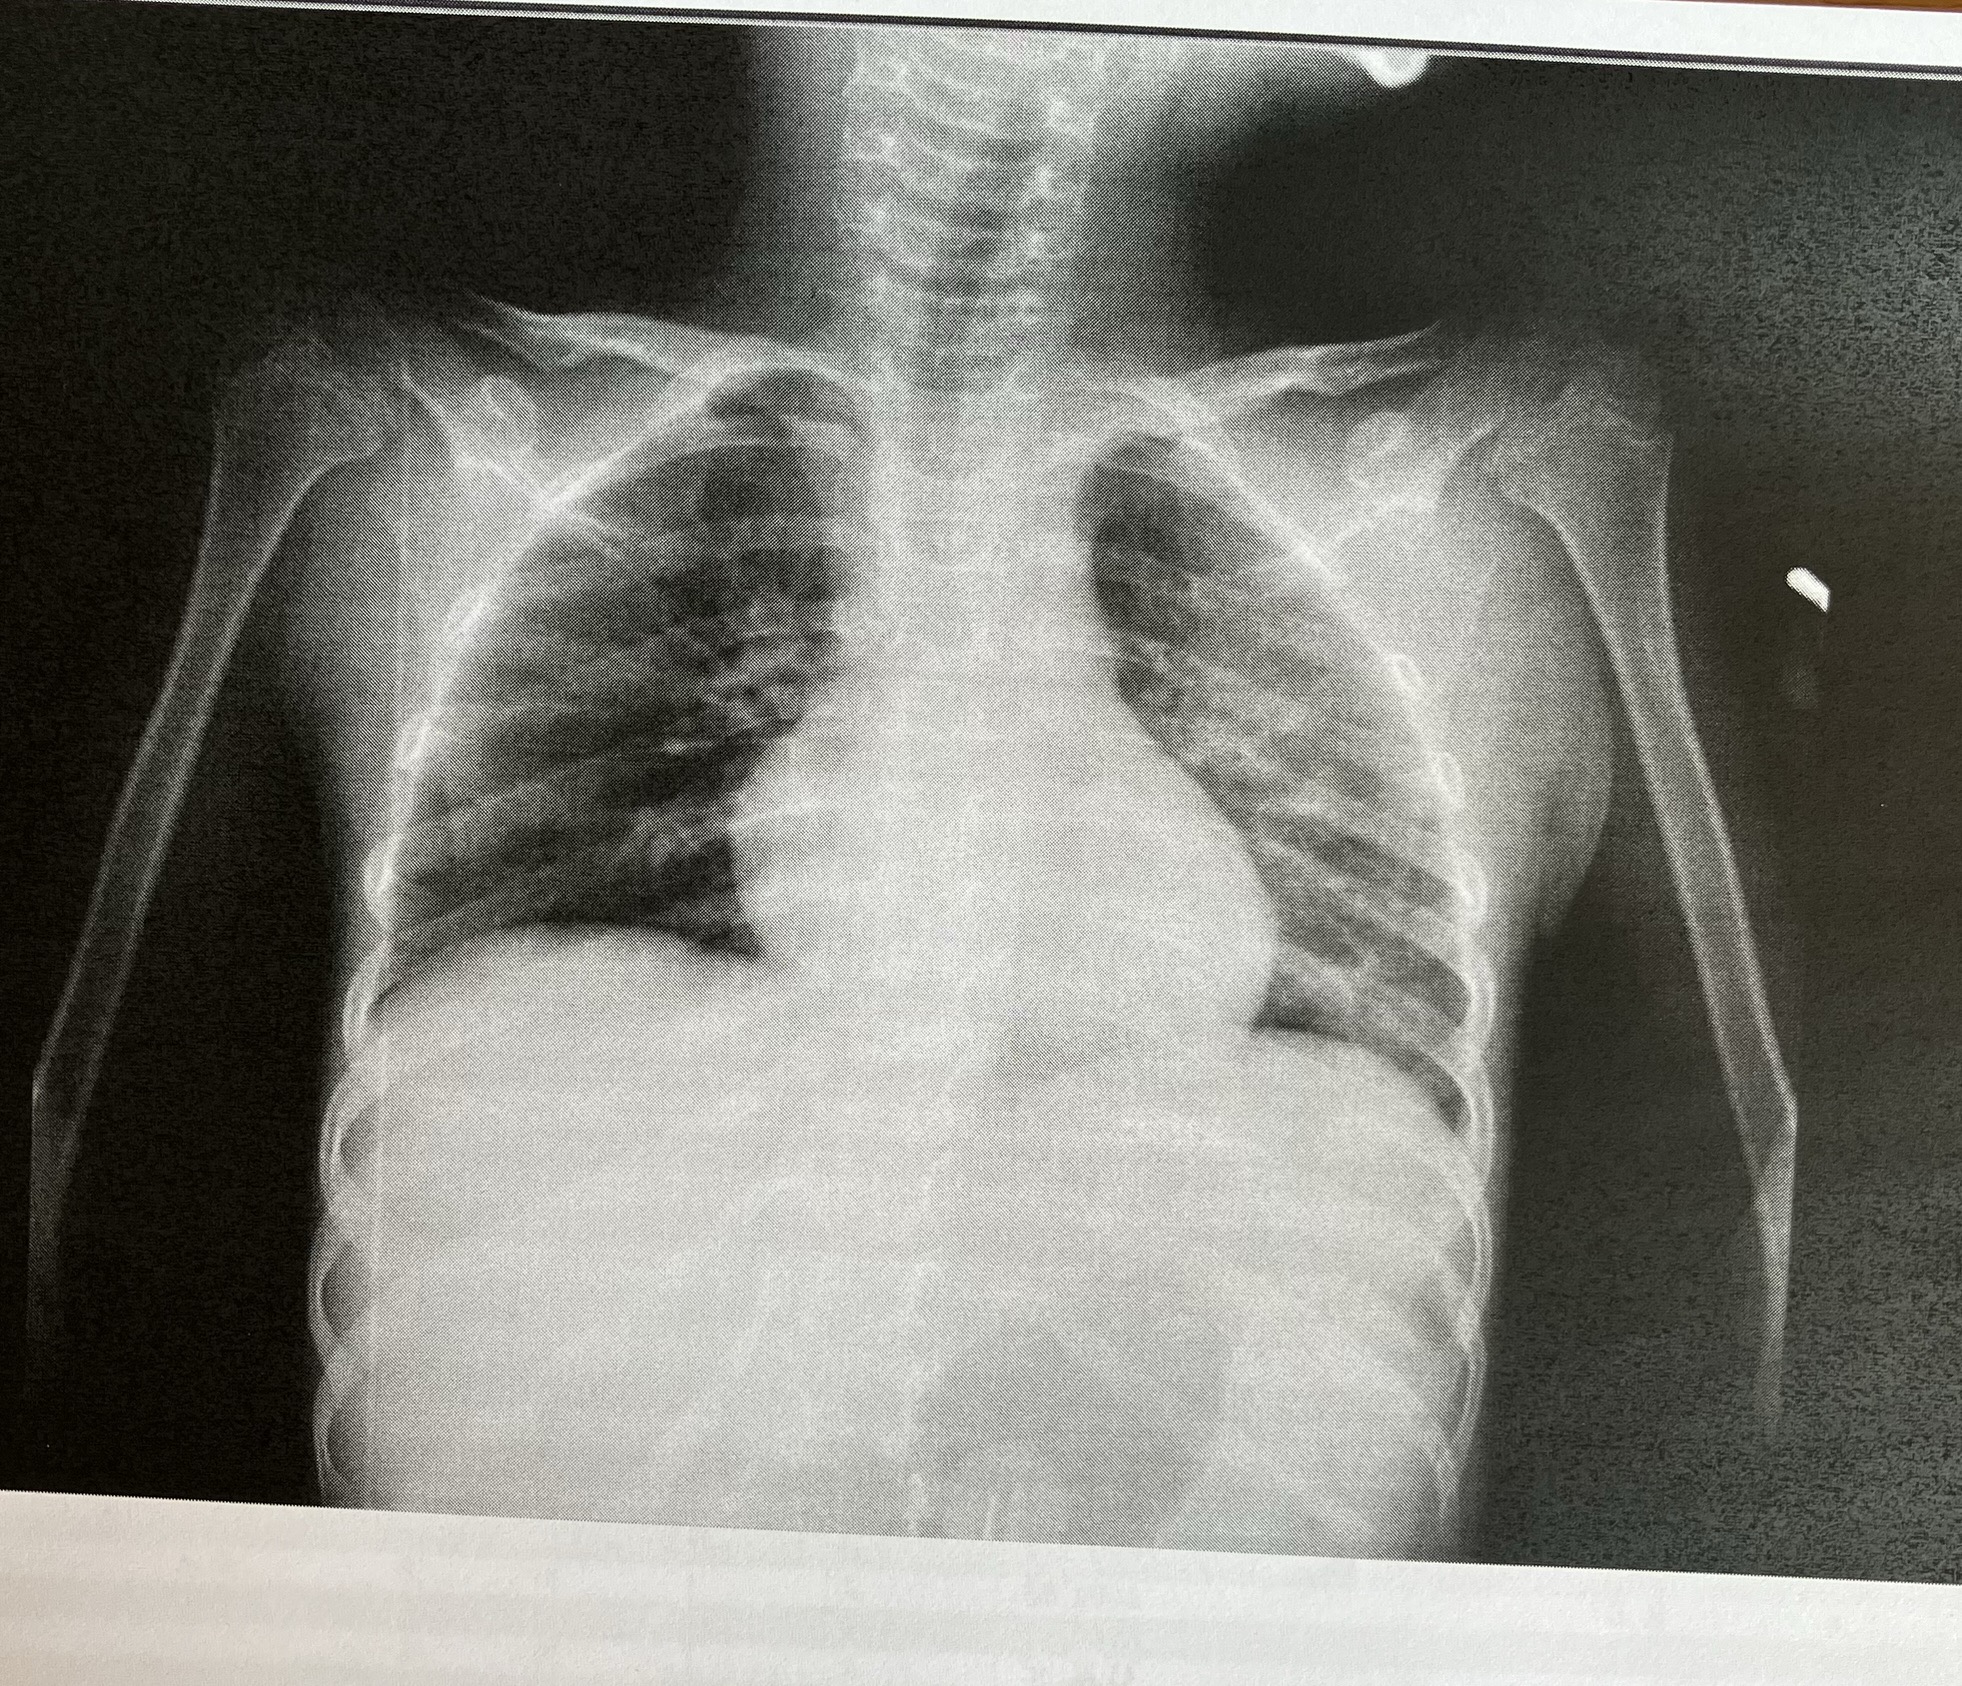

昨日は9時に採血・検尿、レントゲンも撮って、

結果は…

先生「採血とレントゲンを撮ったけど、

まだ左肺が白っぽいのと、炎症値も5と高い。

このまま帰すのは心配だから注射の抗生物質を

しっかり7日間やってから、また結果を見ましょう。

退院は延期です。」

ということで…

退院はもう少し先になりました😢

改善傾向にはあるので、

しっかり治してから帰ろう💪